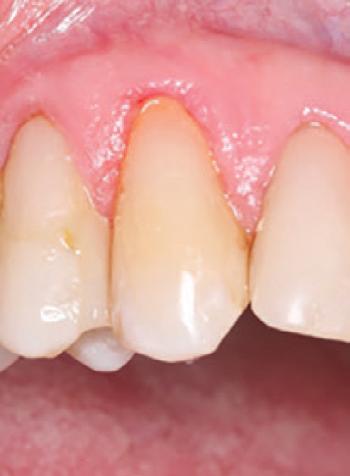

To improve isolation and soft tissue access, a retraction cord was placed before initiating the procedure (Fig. 2). The tooth was evaluated using a caries indicator dye (Kuraray Noritake Dental), helping to identify any remaining infected tissue beneath the dislodged composite (Fig. 3). Decay removal was completed with a diamond bur, and the enamel was bevelled using a starburst pattern to enhance aesthetic blending (Fig. 4). This preparation design was chosen for visual integration rather than bond strength enhancement.